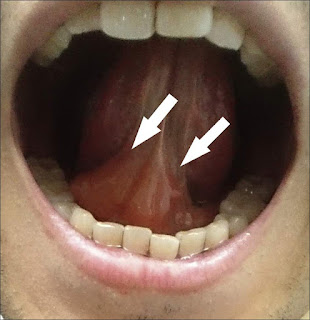

少部分患者會出現輕微至中度的局部過敏反應,像是喉嚨有異物感,咽喉發炎,口腔癢或嘴唇水腫,但繼續治療一段時間後(約1-3個月),這些反應會慢慢消失。這些過敏反應大部分發生在每天剛服用阿克立舌下錠後的5分鐘內,之後反應就會逐漸減輕。

此為舌下水腫的現象,一般會慢慢改善消腫